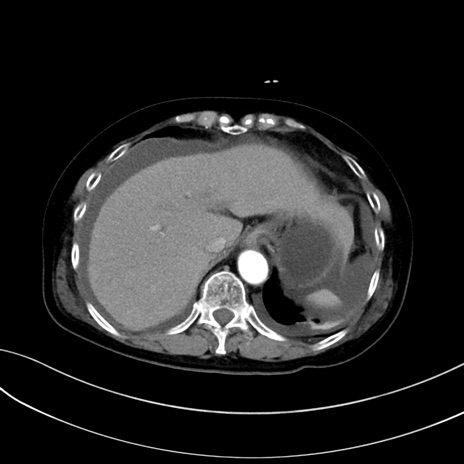

症例13 CT(横断像)1日半後